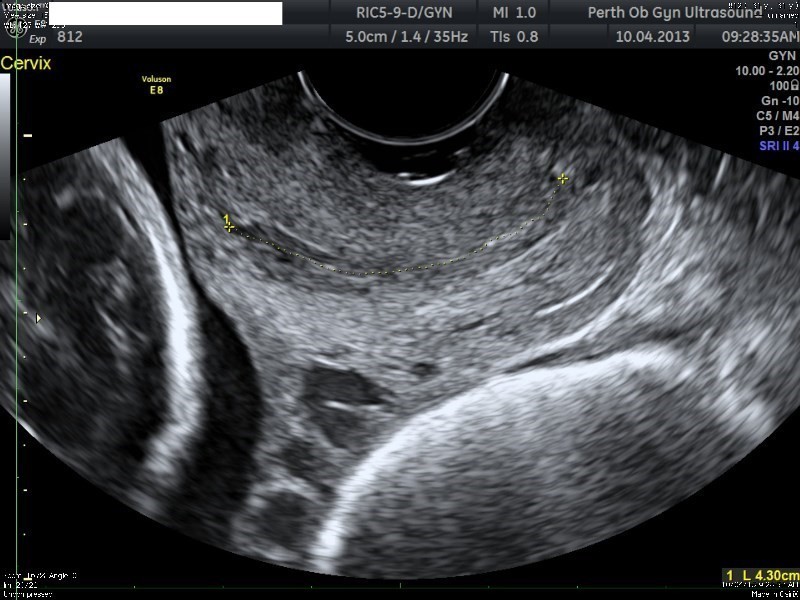

Pour ce faire, un enregistrement cardiotocographique est posé, et une échographie obstétricale par voie endovaginale est à réaliser pour mesure de la cervicométrie. On considère un col raccourci lorsqu’il est mesuré par échographie à moins de 25 mm.

La mesure de la longueur cervicale est réalisée ainsi qu’un monitoring fœtal :

On voit sur l’image le crâne fœtal derrière le col utérin, la présentation est donc céphalique

La mesure du col est à 43 mm, donc long, il n’y a donc pas de menace d’accouchement prématuré vraie

Le diagnostic de rupture prématurée n’est pas fait sur l’échographie du col utérin mais sur l’examen clinique +/- paraclinique (PROM Test)